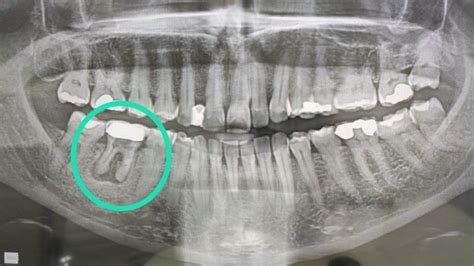

El Absceso Dental: Un Problema Serio

Un absceso dental es el resultado de una infección y puede formarse dentro de las encías, los dientes e incluso en el hueso que sostiene los dientes en su lugar. Es la acumulación de infección y bacterias en una bolsa de espacio, lo que puede causar mucho dolor e incomodidad.

Tipos de Abscesos Dentales

- Absceso dental (absceso periapical): Infección que se ha extendido a la punta de la raíz de un diente.

- Absceso periodontal: Absceso ubicado en la encía, originado por una infección en esta área.